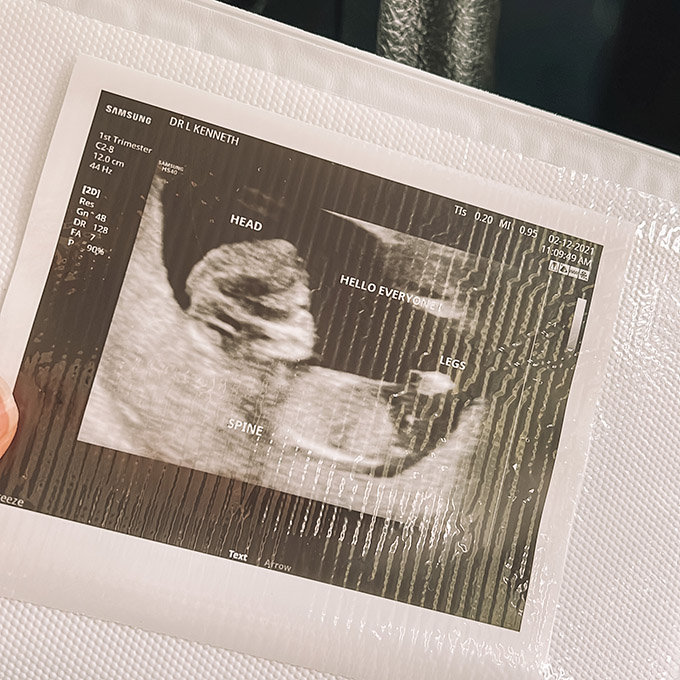

Between weeks 11-13, you will schedule an ultrasound for a nuchal translucency screening. This ultrasound is done on your belly and the technician will be taking some measurements to physically check for chromosomal abnormalities such as Down Syndrome.

NIPT (Noninvasive Prenatal Testing):

I personally opted to have my NIPT done at 12 weeks. It’s a test that can be done anytime after 9 weeks (depending on the lab). It’s a simple blood draw that tests for chromosomal abnormalities (like Down Syndrome) and can also detect the sex of your baby.